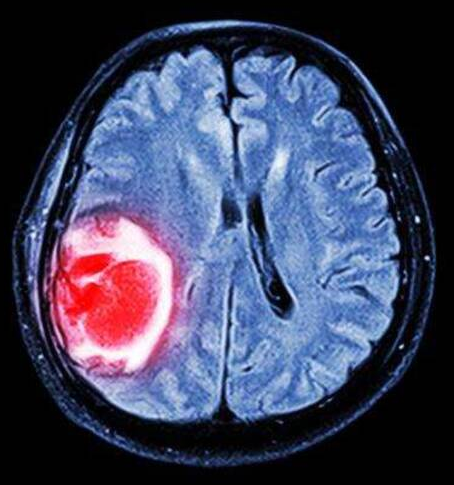

脑部肿瘤

脑部肿瘤是指生长在颅腔的新生物,又称颅内肿瘤、脑癌,可起源于脑、脑膜、神经、血管及脑附件,或由身体的其他组织或脏器转移侵入颅内而形成,大都可产生头痛、颅内高压及局灶性症状。脑瘤的发生率约为1.9~5.4人/(年·10万人),占全身各种肿瘤的1%~3%。

图片来源:网络收集